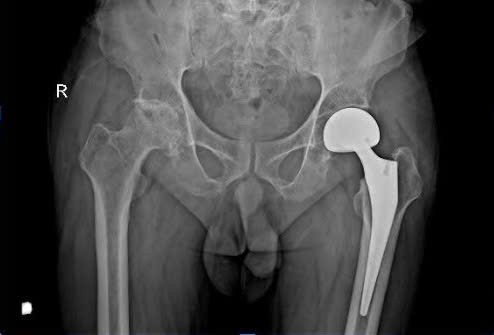

Sau khi thăm khám lâm sàng, chụp X-quang và làm các xét nghiệm cần thiết, các bác sĩ xác định bệnh nhân bị hoại tử chỏm xương đùi phải giai đoạn nặng. Bệnh nhân được chỉ định phẫu thuật thay khớp háng bán phần để loại bỏ phần xương hoại tử, thay thế bằng khớp nhân tạo giúp phục hồi chức năng vận động và giảm đau hiệu quả.

Hình XQuang bệnh nhân đã thay khớp háng bên trái do hoại tử |